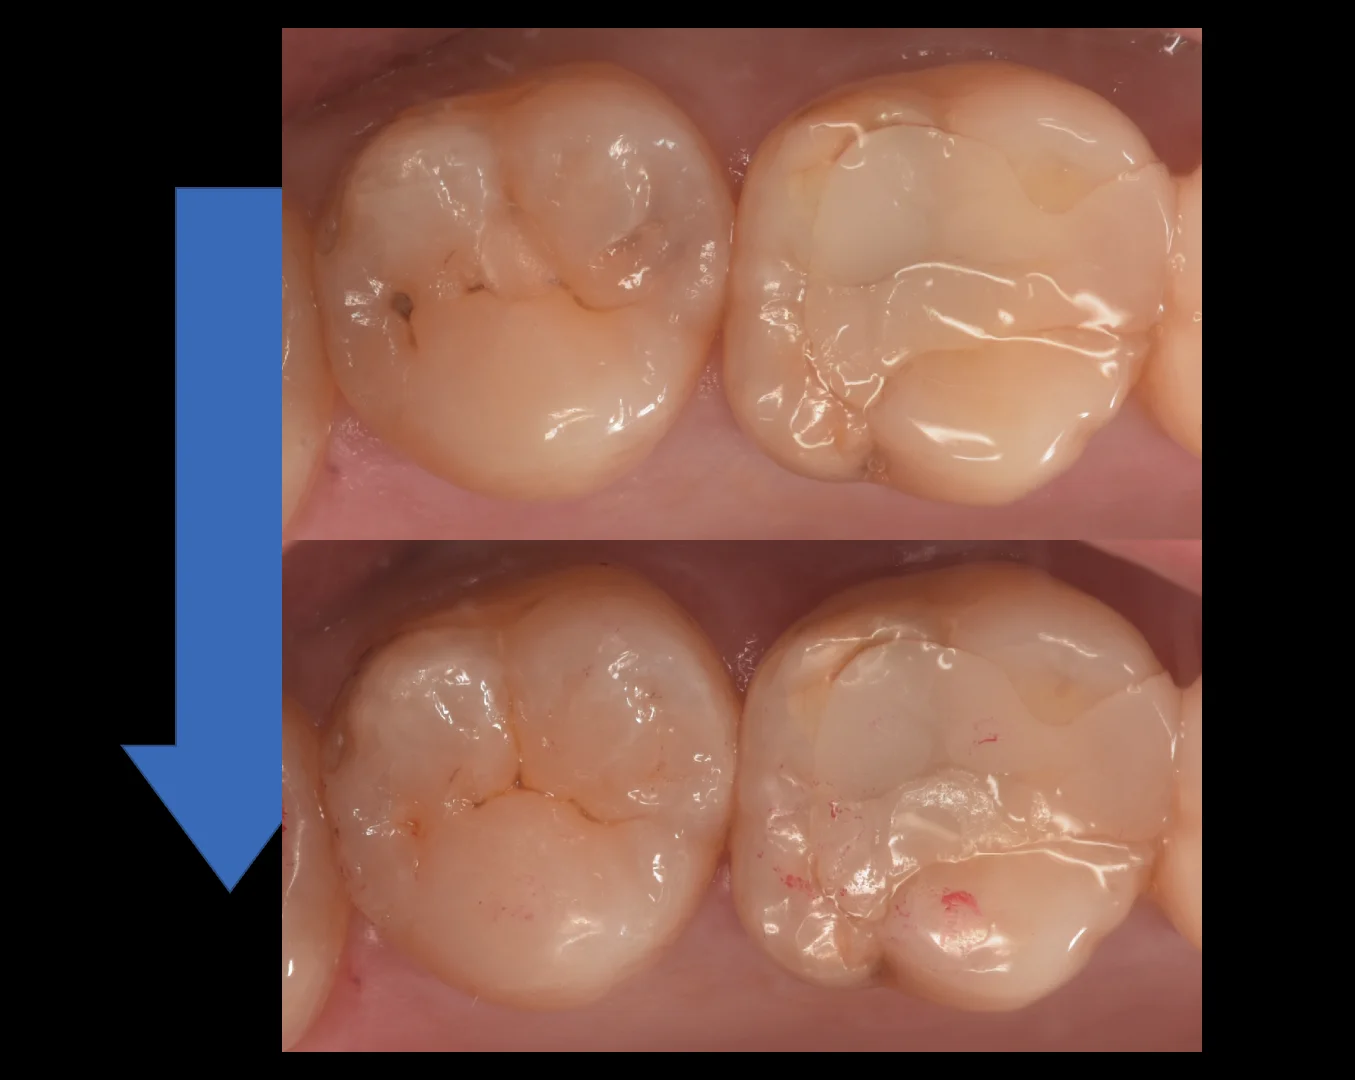

そして詰め終わったのがこちらになります。

どうでしょうか?

違和感なくしっかりと詰め終われたかと思います。

個人的にはかなり良い仕上がりになったと思います。

1週間経って歯の色があってくると拡大視野を使用した歯科医師が診ても一瞬わからないんじゃないでしょうか?!

治療の術前術後がこちらになります。